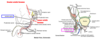

The perineum is the region of the trunk below the pelvic diaphragm and bounded by the pelvic outlet. It is subdivided by a line connecting the ischial tuberosities into 2 triangles that do not communicate. They are:

–anterior urogenital triangle(horizontal)

–posterior anal triangle (almost vertical)

The pudendal nerve & internal pudendal vessels are the main nerve & blood supply of the perineum. The pudendal nerve leaves the pelvis through the…………. and enters the perineum through the………………

greater sciatic foramen

lesser sciatic foramen

Inferior to the………………., the pudendal nerve enters the…………………. canal formed from the obturator internus fascia (below pelvic diaphragm) to travel in lateral wall of ischioanal fossa. It is accompanied by the internal pudendal artery and vein.

ischial spine

pudendal

What are the parts that make up the pudendal nerve (which is a mixed somatic nerve)?

- Inferior rectal nerve to the external anal sphincter and levator ani (GSE) and perianal skin (GSA)

- Perineal nerve

- Dorsal nerve of the penis or clitoris, which is sensory (specially to glans) (GSA)

The perineal nerve (a part of the pudendal nerve) divides into what 2 nerves?

- Cutaneous posterior scrotal or posterior labial branches (GSA) which goes to posterior scrotum or labia.

- Deep perineal nerve (GSE) which goes to skeletal muscles of the superficial and deep perineal pouches, including the external urethral sphincter/skin of vestibule, and mucosa of lower vagina (GSA)